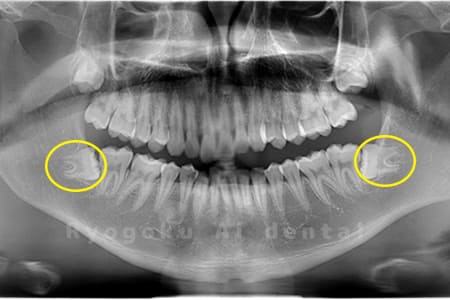

Case01

-

- 原因

- 水平埋伏智歯

- 治療内容

- 下顎の水平埋伏智歯を抜歯

<リスク・副作用>

手術後は痛み、腫れ、痺れなどの副作用が生じる場合があります。